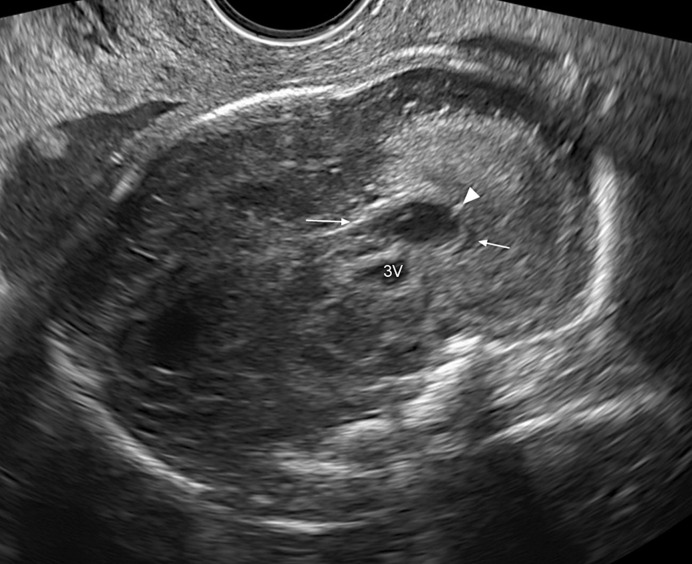

Results: Seventy-two patients were included in our cohort. In 76% infection occurred in the 1st T or periconceptional. In 12 patients, the exact time of infection was inconclusive, including two cases of secondary infection. In 34.7%, a callosal anomaly was observed and it was never isolated. CNS abnormalities included: periventricular hyperechogenicity (PVHE) 55.5%, calcifications 52%, ventriculomegaly 33%, periventricular pseudocysts 31.4%, occipital cysts 22.2%, echogenic ganglionic eminence 30.5%, lentostriatal vasculopathy 26.4%, sulcation abnormalities 22.2%, cerebellar findings 18% and HC below -2 SD 18%. In 19 cases, the CC was short with calcifications in four. In one case, the insult was severe and in another the CC was absent. The most common association with CC insult was PVHE (56%) and calcifications (52%).

Abstract Image